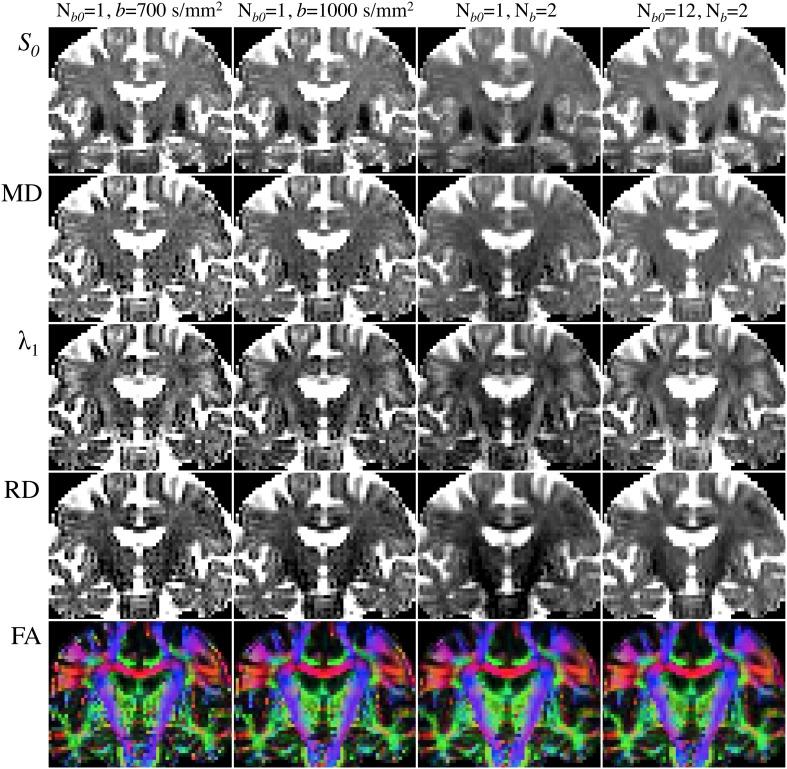

Glucose hypometabolism and gray matter atrophy are well known consequences of Alzheimer's disease (AD). Studies using these measures have shown that the earliest clinical stages, in which memory impairment is a relatively isolated feature, are associated with degeneration in an apparently remote group of areas-mesial temporal lobe (MTL), diencephalic structures such as anterior thalamus and mammillary bodies, and posterior cingulate. These sites are thought to be strongly anatomically inter-connected via a limbic-diencephalic network. Diffusion tensor imaging or DTI-an imaging technique capable of probing white matter tissue microstructure-has recently confirmed degeneration of the white matter connections of the limbic-diencephalic network in AD by way of an unbiased analysis strategy known as tract-based spatial statistics (TBSS). The present review contextualizes the relevance of these findings, in which the fornix is likely to play a fundamental role in linking MTL and diencephalon. An interesting by-product of this work has been in showing that alterations in diffusion behavior are complex in AD-while early studies tended to focus on fractional anisotropy, recent work has highlighted that this measure is not the most sensitive to early changes. Finally, this review will discuss in detail several technical aspects of DTI both in terms of image acquisition and TBSS analysis as both of these factors have important implications to ensure reliable observations are made that inform understanding of neurodegenerative diseases.

葡萄糖代谢低下和灰质萎缩是阿尔茨海默病(AD)的已知后果。使用这些测量方法的研究表明,在最早的临床阶段,记忆障碍是一个相对孤立的特征,与中颞叶(MTL)、间脑结构(如前丘脑和乳头体)和后扣带的一组明显远程区域的退化有关。这些部位被认为通过边缘-间脑网络在解剖学上紧密相连。弥散张量成像或 DTI-一种能够探测白质组织微观结构的成像技术-最近通过一种称为基于束的空间统计学(TBSS)的无偏分析策略,证实了 AD 中边缘-间脑网络的白质连接退化。本综述将这些发现的相关性置于上下文中,其中穹窿可能在连接 MTL 和间脑方面发挥着重要作用。这项工作的一个有趣的副产品是,AD 中的扩散行为改变是复杂的-虽然早期研究倾向于关注分数各向异性,但最近的研究强调,这种测量方法对早期变化不是最敏感的。最后,本综述将详细讨论 DTI 的几个技术方面,包括图像采集和 TBSS 分析,因为这两个因素对确保进行可靠的观察以了解神经退行性疾病都有重要的影响。